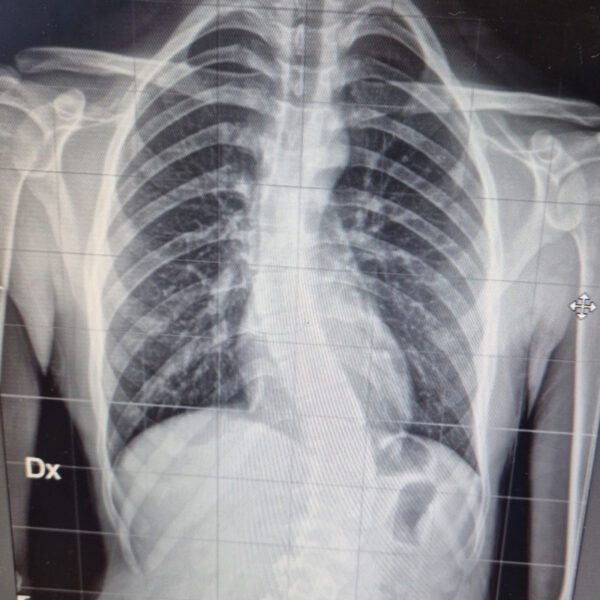

DIAGNOSI:

IPERCIFOSI DORSALE + SCOLIOSI DORSO LOMBARE

Radiografia della colonna in toto pre-operatoria

Intervento chirurgico eseguito:

STABILIZZAZIONE DORSO – LOMBARE CON OSTEOTOMIE CORRETTIVE

Radiografia della colonna in toto post-operatoria